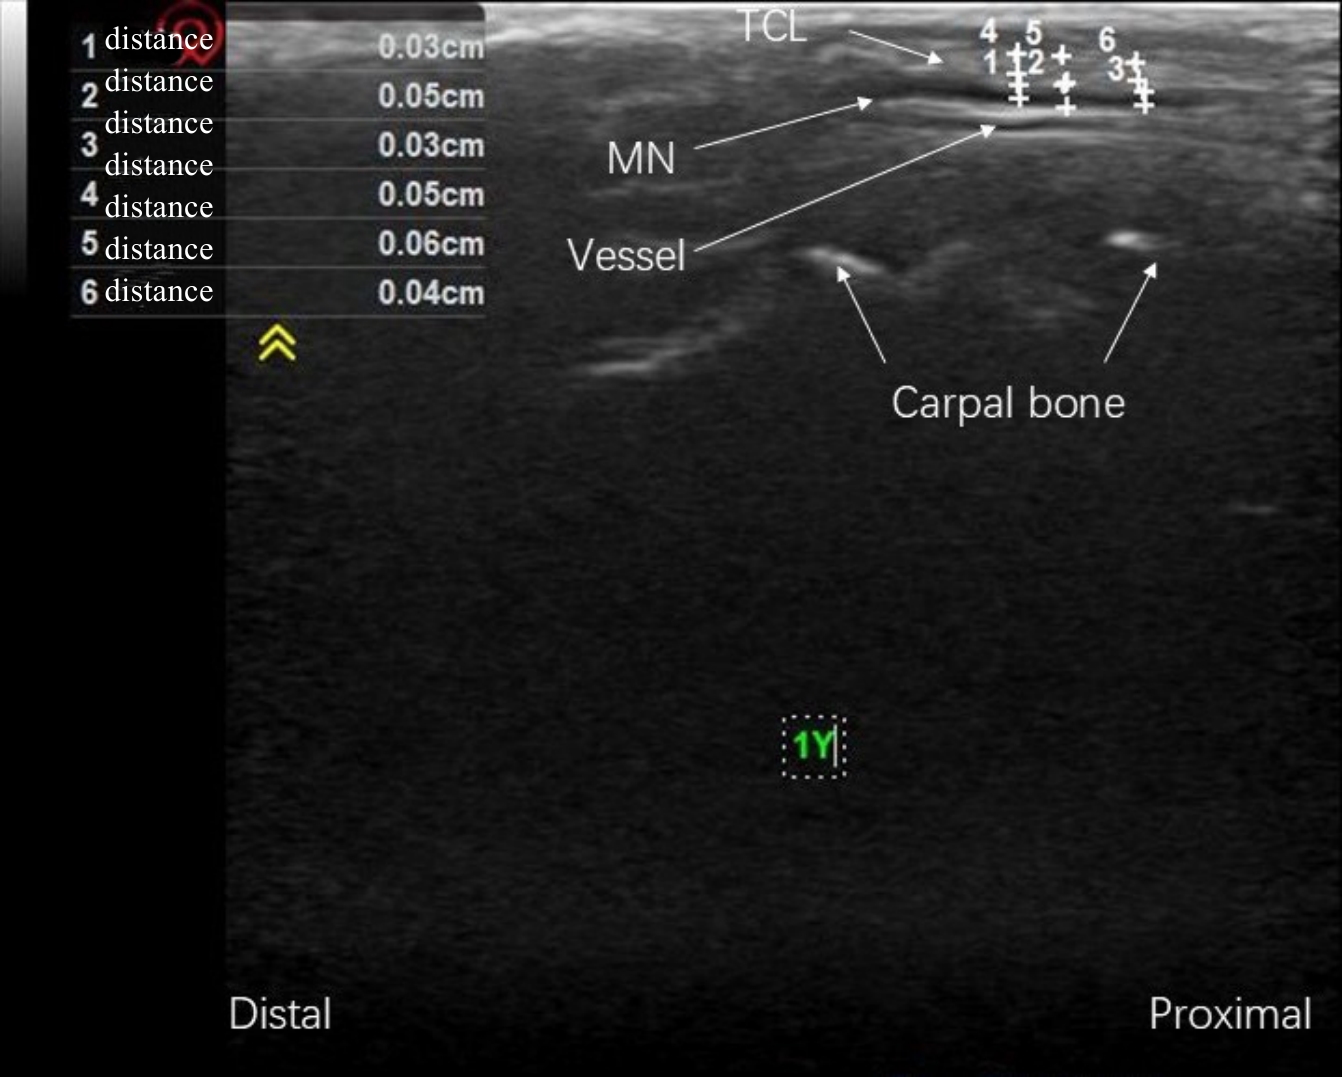

Tab.1 Thickness of the MN of the rabbits in the 5 groups (cm, Mean±SD)

Tab.2 Thickness of TCL of the rabbits in the 5 groups (cm, Mean±SD)